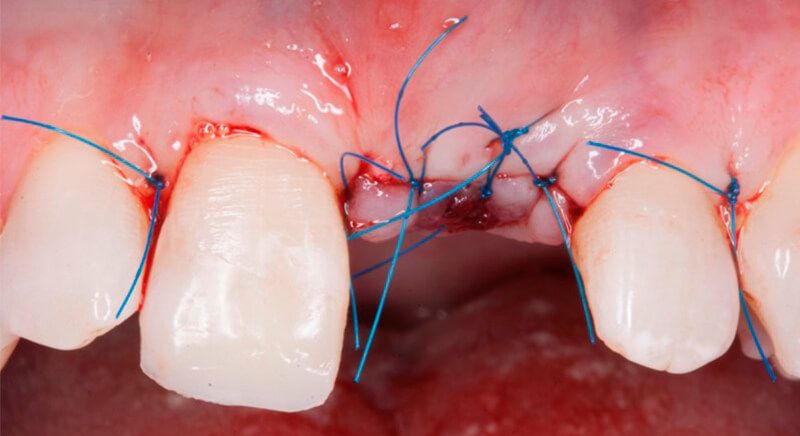

The guided surgery was performed by lifting a full thickness mucoperiosteal flap. A Biomimetic Ocean CC implant, diameter 3.5mm and length 10mm, was inserted using the surgical guide in the ideal three-dimensional position and the defects were regenerated with xenograft and reabsorbable membrane, the nasopalatine duct on the palatine side and the area of dehiscence on the vestibular.

During the same surgical intervention, a short 3mm Avinent healing abutment was positioned and fully covered by the flap. Primary closure was completed and we waited 6 months for the bone graft to mature.